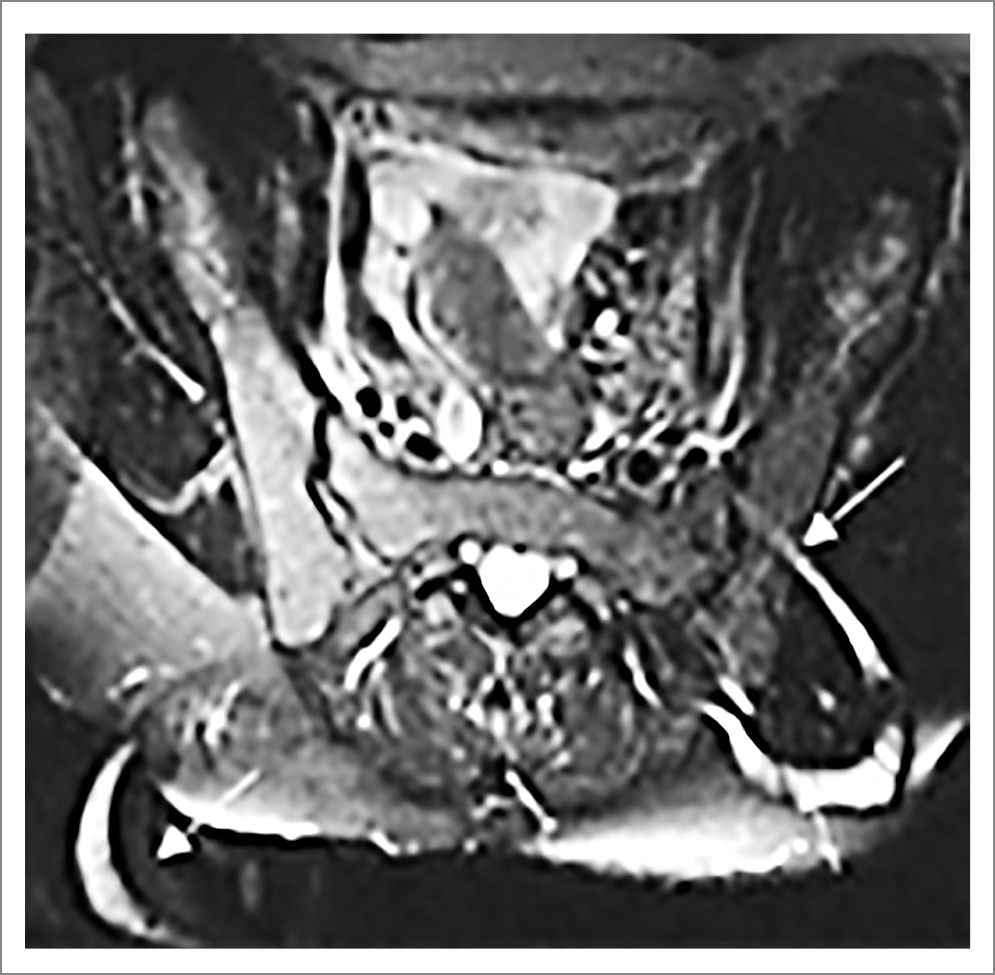

Рис. 10. Пациент Б., диагноз АС. МРТ КПС (коронарная проекция, режим Т2 FatSat): множественные зоны отека костного мозга (указаны стрелками) в основном в субхондральных областях. Изменения соответствуют критериям «активного» сакроилиита по классификации ASAS [22].